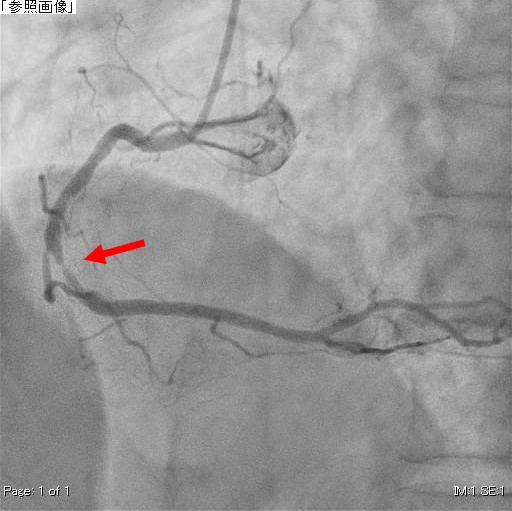

右冠動脈造影(治療前)

矢印の狭窄により心筋への血流が少なくなっている